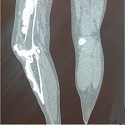

La mélorhéostose

Kawtar Nassar, Ouafa Mkinsi

PAMJ. 2014; 19: 314. Published 21 November 2014